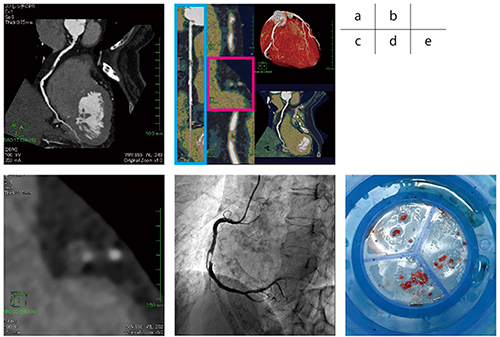

冠動脈CT検査では,右冠動脈#2に狭窄率75〜90%の重度狭窄を認めた(図1 a)。さらにプラーク性状を観察すると,病変部は陽性リモデリングを呈し,内部にソフトプラークを認め(図1 b),さらに短軸像にてリング様所見(napkin-ring sign,ring like sign)を認め(図1 c),不安定病変の存在が疑われた。心臓カテーテル検査では右冠動脈#2に狭窄率75〜90%の重度の狭窄を認め(図1 d),経皮的冠動脈形成術(PCI)を施行した。冠動脈CT検査の所見よりプラーク性状は脆弱なプラーク(vulnerable plaque)が疑われるため,体外式ペーシング,末梢保護デバイスを用いて手技を施行した。前拡張を行ったところ末梢塞栓と思われる心電図ST上昇,slow flowを認めたため,塞栓吸引(図1 e)を行いflowを改善して終了した。

図1 症例1:狭心症(70歳代,女性)

a:右冠動脈のCPR画像。#2に重度の狭窄を認める。

b:右冠動脈ストレート画像(□),短軸像のカラーマッピング画像(□)。狭窄部の陽性リモデリング,プラークの一部にlow density plaqueを認める。

c:短軸像にて不安定プラークの特徴と報告されているnapkin-ring signを認める。

d:心臓カテーテル検査にて右冠動脈#2に重度狭窄を認める。

e:PCI施行中に吸引された赤色血栓